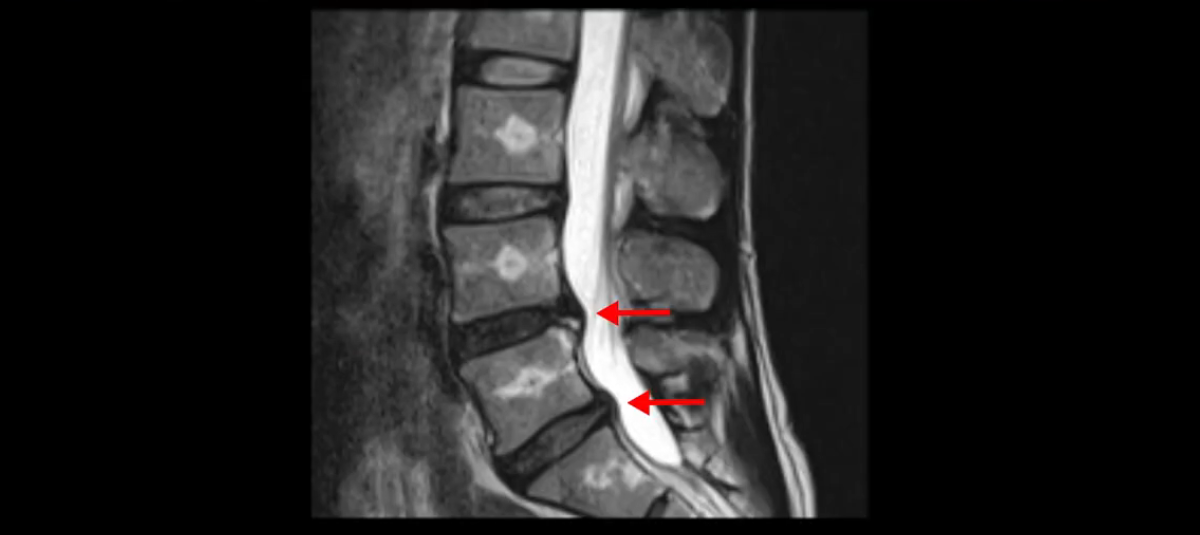

이분 MRI를 보시면 두 마디의 퇴행성디스크가 있습니다. 그리고 디스크가 조금씩 밀려 나와 있고요. 그런데 디스크 탈출 정도는 두 마디 다 심하지 않습니다. 4번 5번에는 디스크 탈출이 약간 있고,

척추관협착도 약간 진행이 되고 있고요.

5번 1번은 디스크 탈출이 가운데 쪽으로 살짝 있습니다.

또한 양쪽 신경 가지가 빠져나가는 추간공은 매우 넓은 상태입니다.

중요한 것은 이 정도 경미한 탈출과 협착으로는 양쪽 다리가 저리고 아플 수가 없습니다.

그리고 만약에 이 디스크가 급성으로 찢어진 것이라면 아주 심한 디스크성 통증이 있겠죠. 기침이나 재채기를 하면 심하게 아프고 허리를 조금만 구부려도 아주 날카로운 통증들이 생길 겁니다. 그런데 이분은 이런 증상이 전혀 아닙니다. 디스크의 돌출 정도와 협착이 전혀 심하지 않기 때문에 이분이 가지고 계신 양쪽 다리 저림, 특히 이분은 누워있을 때도 양쪽 다리가 저리다고 하는데, 디스크 때문에 그런 증상은 생길 수가 없습니다. 또 이 디스크는 오래된 디스크, 이미 찢어진 섬유륜이 아문 디스크이고, 그러니까 이분은 기침이나 재채기를 못하는 증상이 없는 거죠. 그 다음에 허리를 구부릴 때 뻐근한 증상은 있지만 아주 날카로운 통증은 없습니다.

이분 MRI를 보시면 퇴행성디스크가 있고 약간의 협착이 있지만 이 정도의 퇴행성디스크와 협착으로는 신경이 눌려서 양쪽 다리가 저리고 아픈 증상이 나올 수가 없습니다. 그래서 MRI와 이 환자분의 다리 증상이 매치가 안 된다고 하는 의사들이 많은 겁니다.